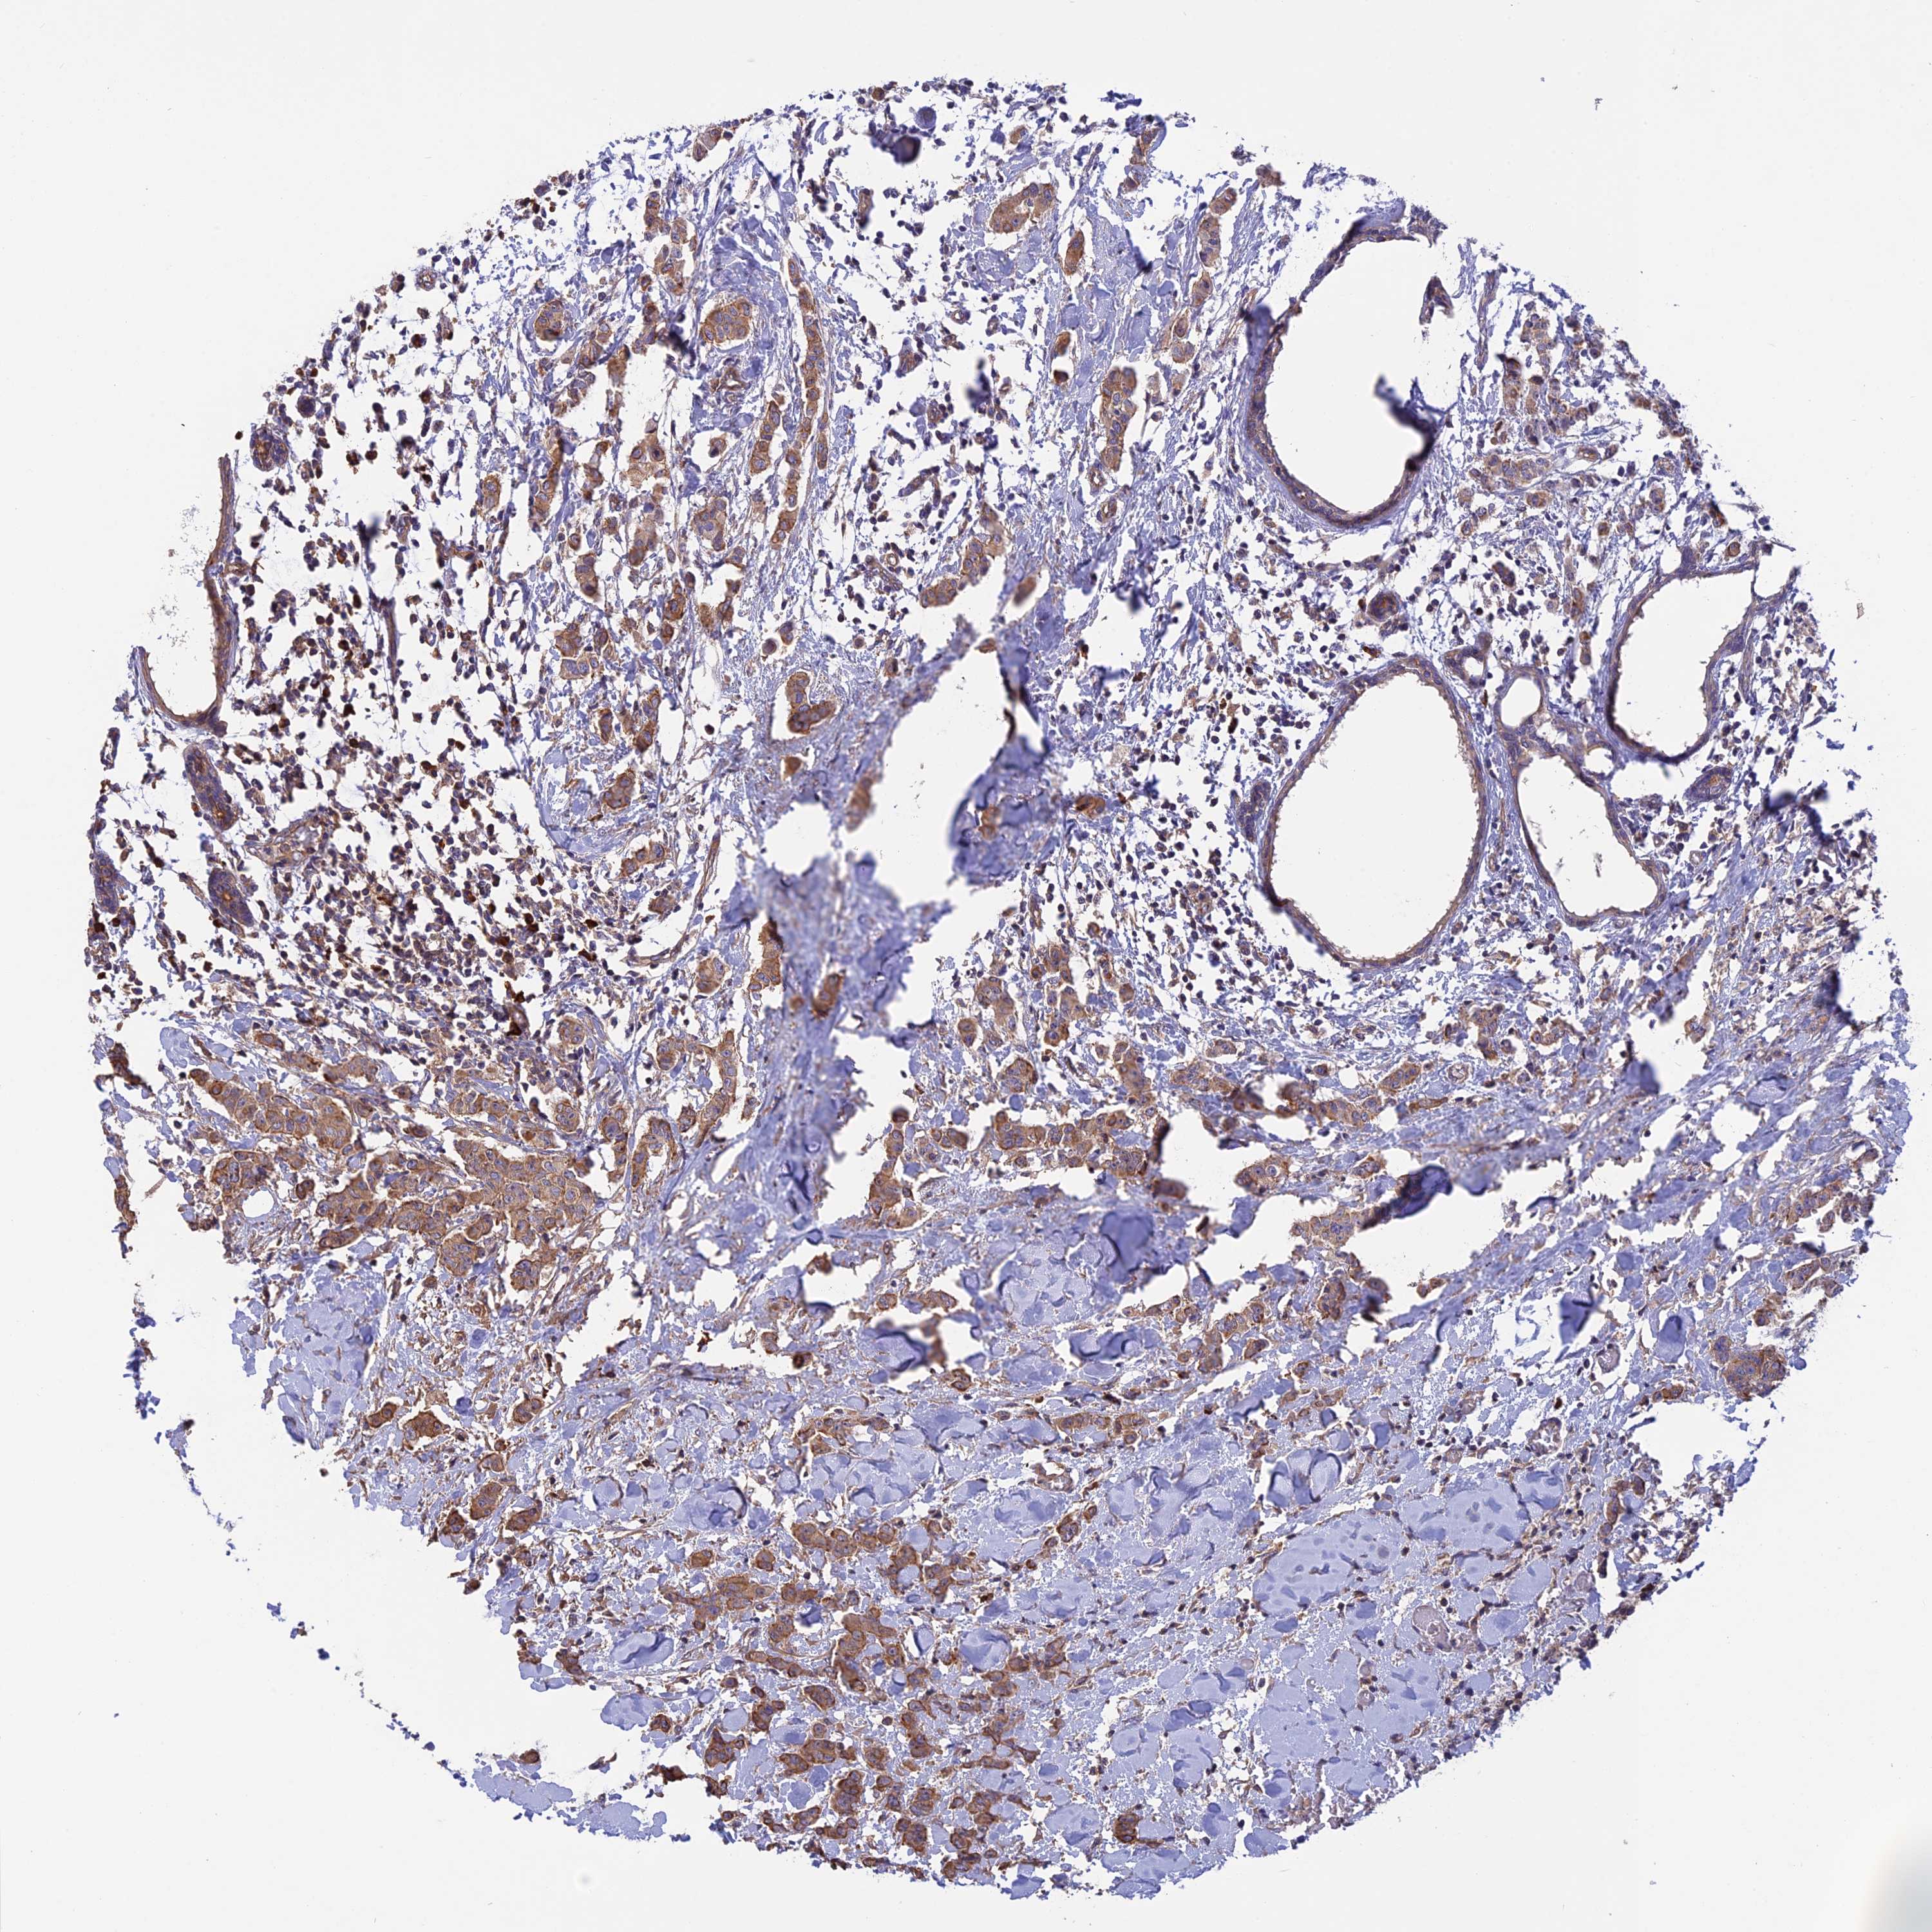

CANCER BREAST CANCER Show tissue menu

BRCA TCGA BRCA VALIDATION PROTEIN EXPRESSION